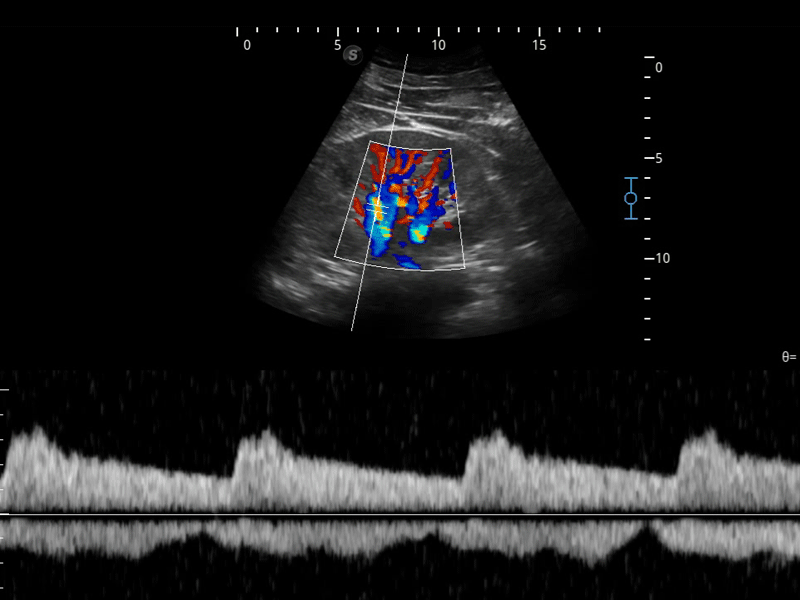

凭借狗万官方网站先进的成像技术和优异的探头技术提供的清晰的图像表现,您可以更自信地做出临床决策。